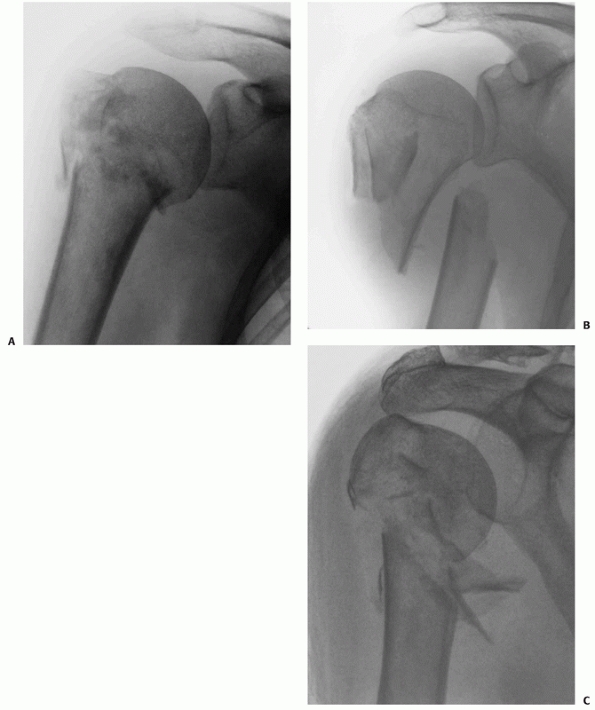

![]() |

FIGURE 35-14

Three- and four-part impacted valgus fractures show considerable variation radiologically and on three-dimensional computed tomography reconstructions (as shown), ranging from fractures that are minimally displaced (A), through more severe valgus angulation (B) to displacement with lateral translation of the head, where the medial soft tissue hinge is disrupted (arrow) and the risk of osteonecrosis is higher (C,D). |

FIGURE 35-15

Three- and four-part varus fractures are less common than valgus injuries, and radiologically give rise to inferior subluxation of the humeral head on conventional radiography (A) and on three-dimensional reconstructions of computerised tomograms (B). |